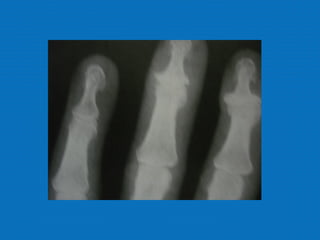

RADIOLOGIA

No início da doença não se observam anormalidades. Com seu

desenvolvimento, observam-se:

• Diminuição do espaço intra-articular

• Esclerose subcondral (eburnação)

• Osteófitos;

• Erosão e anquilose óssea (pseudocistos ósseos).

RADIOLOGIA No início dadoença não se observam anormalidades. Com seu desenvolvimento, observam-se: • Diminuição do espaço intra-articular • Esclerose subcondral (eburnação) • Osteófitos; • Erosão e anquilose óssea (pseudocistos ósseos).